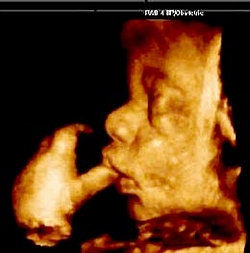

Palabras del Santo padre durante la Vigilia por la Vida Naciente

Benedicto XVI: «El embrión humano no es un cúmulo de material biológico sino

un nuevo individuo de la especie humana»

Al presidir el pasado sábado la Vigilia por la Vida

Naciente que convocó para toda la Iglesia, el Papa Benedicto XVI exhortó a

proteger la vida de todo ser humano siempre, desde su concepción hasta la

muerte natural, ante todo tipo de amenaza como el aborto. Toda persona humana,

desde que es embrión, debe ser amada y respetada, señaló.